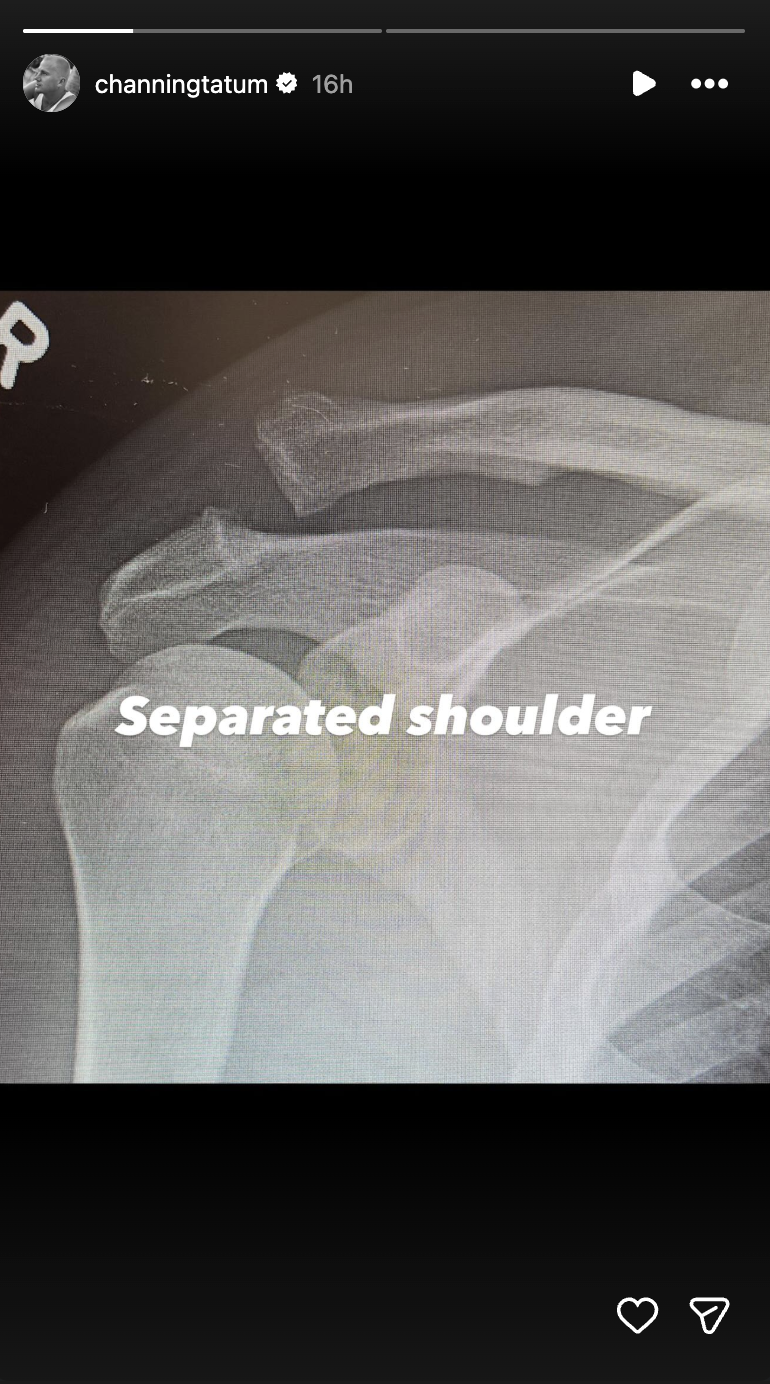

Les réponses sont venues plus tard. Dans une série de stories Instagram, Tatum a partagé des radiographies montrant la blessure et son traitement chirurgical, précisant que son séjour à l'hôpital était lié à une épaule disloquée qui nécessitait une intervention médicale.

Channing Tatum documente sa blessure | Source : Instagram/channingtatum